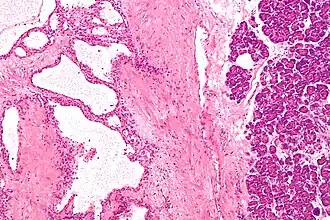

Micrografia de um cistoadenoma seroso do pâncreas; coloração H&E.

Cistoadenoma seroso do pâncreas é um tumor benigno do pâncreas. Geralmente situa-se na cabeça do pâncreas,[1] e pode estar associado com a síndrome de von Hippel-Lindau.[2] Ao contrário de outros tumores císticos do pâncreas, as neoplasias císticas serosas são quase sempre beningnas, embora existam casos raros de cistoadenocarcinomas serosos malignos.[3]